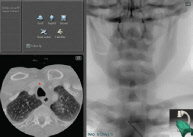

Real-time CT images

PROcedure Rehearsal Studio’s real-time CT images correspond to active fluoroscopic views to help you understand your patient’s anatomy and to assist in effective CT interpretation and study.